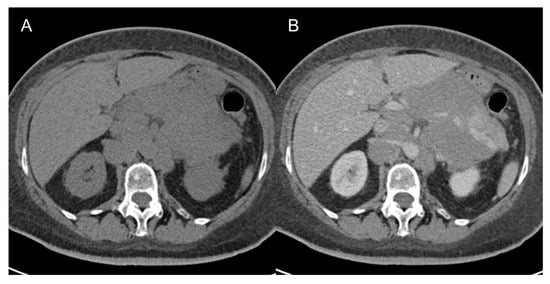

- Well-differentiated liposarcomas (Figure 1) are low-grade tumors. Characteristic CT features include macroscopic fat in at least 75% of the whole tumor with smooth and lobular margins, thick septa (>3 mm), tendency to be nodular, and mild or inconstant low enhancement [5,37,38,39,40]. Calcifications are rare [34] and can indicate dedifferentiation or inflammation. These tumors can recur, but do not tend to metastasize [5].

Figure 1. Well-differentiated retroperitoneal liposarcoma in a 71-year-old man. Axial (A) and coronal (B) contrast-enhanced CT images in the venous phases show a 13.3 cm fat-attenuating mass adjacent to the left psoas muscle, with thin septa (arrow). The lesion was histologically confirmed after surgical excision.